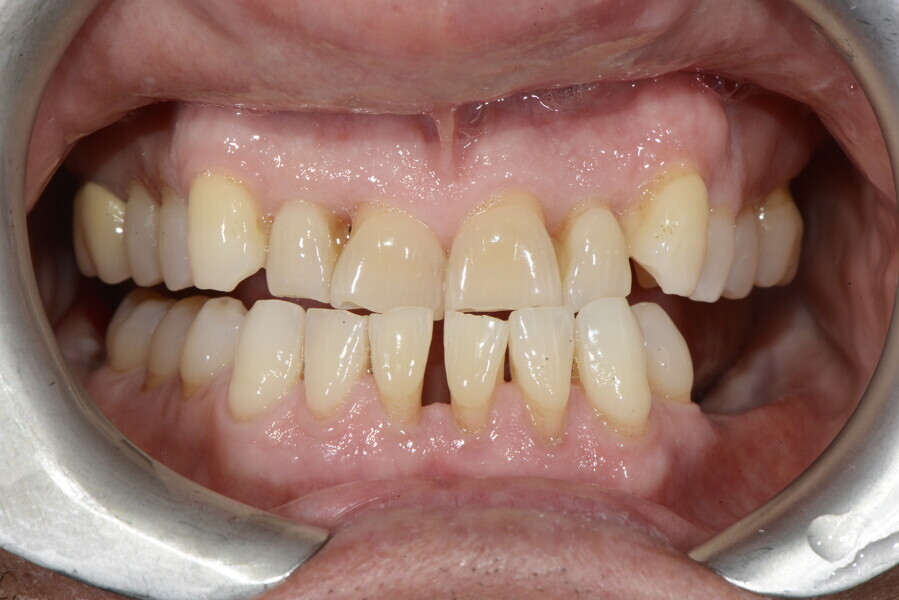

The 58-year-old patient wished to improve his oral aesthetics and function, complaining of mobility of the posterior teeth and wear of the anterior teeth. After data collection, a very complex situation was identified (Figs. 11–13):

1. severe periodontitis with poor prognosis of some teeth;

2. anterior crossbite;

3. severe wear mainly of the anterior teeth and compensatory eruption;38

4. atypical swallowing and lower posture of the tongue at rest;

5. masticatory dysfunction during the mastication test; and

6. no significant signs of temporomandibular disorder.